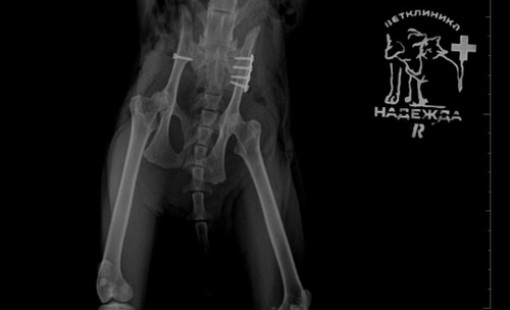

Случаи из практики

Ветеринарная клиника Надежда

За более чем 30-ти летнюю практику наши ветеринары сталкивались в различными случаями болезней и травм животных. Это дало нам огромный опыт в лечении и реабилитации. Мы беремся даже за самые сложные случаи! С любовью и заботой относимся к животным, стараемся сделать так, чтобы они испытывали минимум дискомфорта во время лечения и реабилитации.